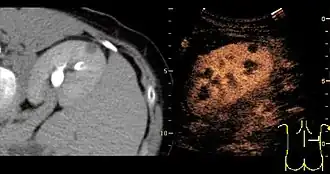

Unspecific cortical lesion on CT is confirmed cystic and benign with contrast-enhanced renal ultrasonography using image fusion.[1]